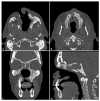

Drug-induced or associated vasculitis is a prevalent form of vasculitis that resembles primary idiopathic antineutrophil cytoplasmic autoantibody (ANCA) vasculitis (AAV). Cocaine is a diffuse psychostimulant drug and levamisole is a synthetic compound used to cut cocaine. Their abuse may result in a spectrum of autoimmune manifestations which could be categorized into three overlapping clinical pictures: cocaine-induced midline destructive lesion (CIMDL), levamisole-adulterated cocaine (LAC) vasculopathy/vasculitis, and cocaine-induced vasculitis (CIV). The mechanisms by which cocaine use leads to disorders resembling AAV are not well understood. Cocaine can cause autoimmune manifestations ranging from localized nasal lesions to systemic diseases, with neutrophils playing a key role through NETosis and ANCA development, which exacerbates immune responses and tissue damage. Diagnosing and treating these conditions becomes challenging when cocaine and levamisole abuse is not suspected, due to the differences and overlaps in clinical, diagnostic, therapeutic, and prognostic aspects compared to primary idiopathic vasculitides.